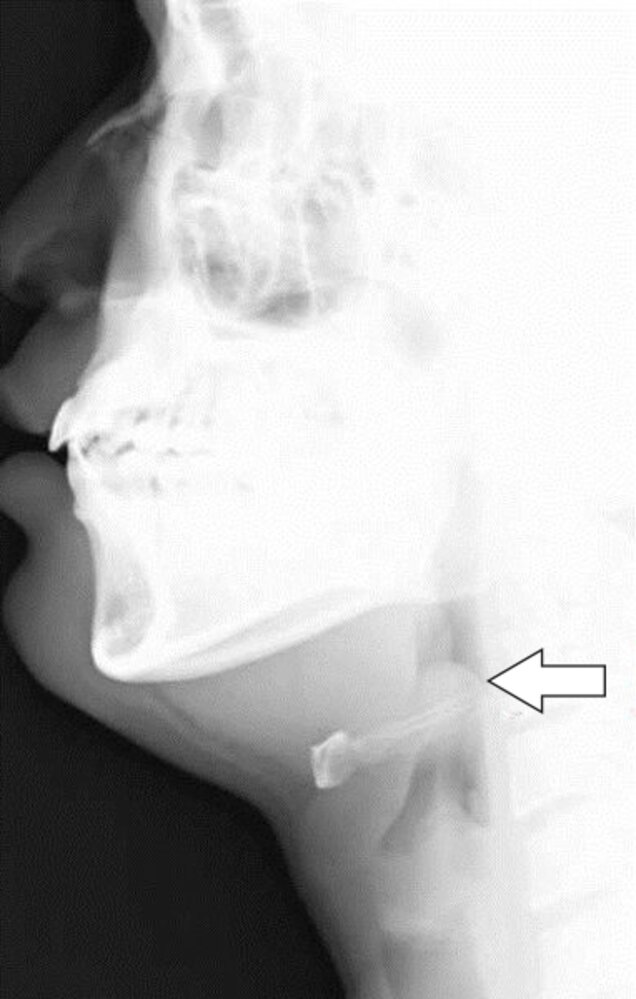

Epiglottitis Knowledge Amboss

Pediatric Epiglottitis Clinical Presentation History Physical Examination